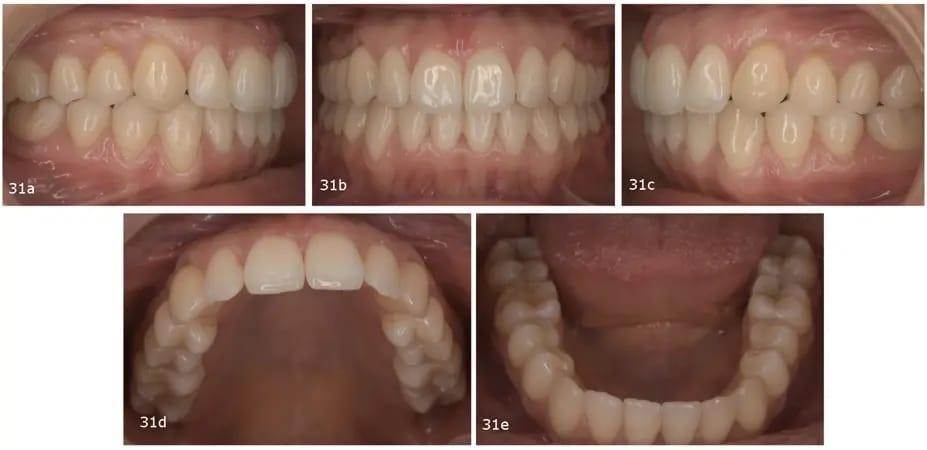

Обе дуги имели улучшенную форму (увеличились примерно на 1,5 мм с каждой стороны), хорошо выровненные зубы и была устранена первоначальная скученность. Были достигнуты двусторонние взаимоотношения коренных зубов и клыков I класса, а также хороший конечный прикус. Резцы верхней челюсти были наклонены (U1–PP от 93° до 106°), а резцы нижней челюсти были слегка втянуты (IMPA от 99,4° до 97,2°). Средние линии были расположены по центру (фото 31).

Фото 31a–e: Послеоперационные интраоральные фотографии.